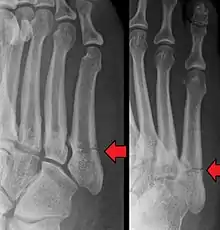

- Proximal diaphysis, typically stress fracture.[12][13]

- Metaphysis: Jones fracture[14]

-Tuberosity: Pseudo-Jones fracture[15] (avulsion fracture).[15]

Normal anatomy:

- Apophysis: Normal at 10 - 16 years.[16]

- Os vesalianum, an accessory bone.[17]

Other proximal fifth metatarsal fractures exist, although they are not as problematic as a Jones fracture. If the fracture enters the intermetatarsal joint, it is a Jones fracture. If, however, it enters the tarsometatarsal joint, then it is likely an avulsion fracture caused by pull from the fibularis brevis tendon. An avulsion fracture at the base of the fifth metatarsal is sometimes called a "dancer's fracture" or a "pseudo Jones fracture", and usually responds readily to non-operative treatment.[18] The X-ray appearance of the developmental "apophysis" in this area may have some resemblance of a fracture, but is not a fracture; it is the secondary ossification center of the metatarsal bone. It is a normal finding that occurs at this site in adolescents.[19] If an injury to that area has occurred, the physician is often able to interpret certain radiographic clues to make the differentiation. An avulsion fracture at this location is typically extra-articular and oriented transversally as compared to the longitudinal orientation of an unfused apophysis.[19]